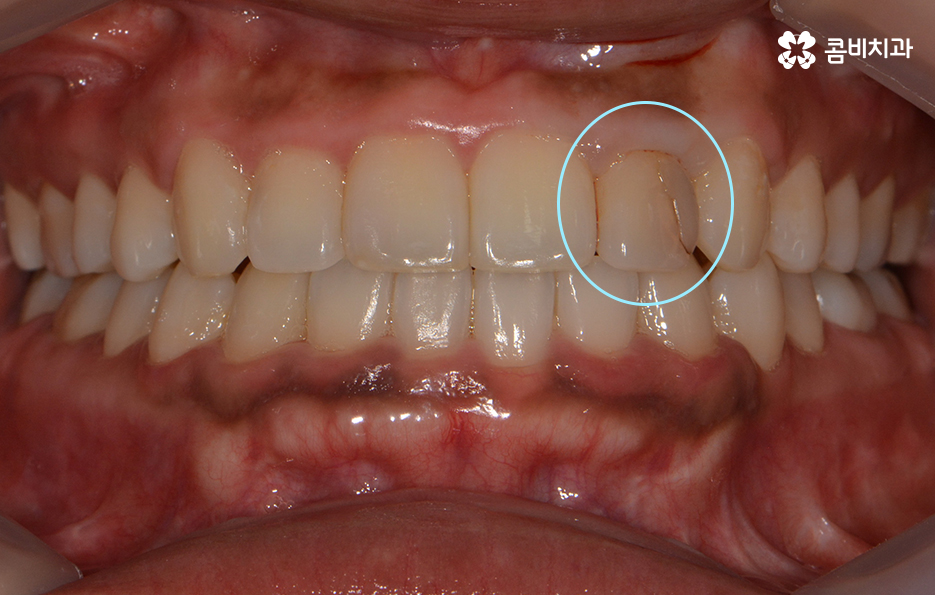

위 환자분의 경우 기존에 타 치과에서 치료받으셨던

라미네이트가 깨져서 내원하셨습니다.

앞니 충치치료 후 레진이나 라미네이트가 깨지는 사례가

종종 있는데 치료 후에는 평상시 생활 습관에 있어서

주의가 필요하며 이 악물기와 같은 습관이 있으신 경우

검사를 통해 개선 방안과 원인을 찾아보는 게 좋습니다.